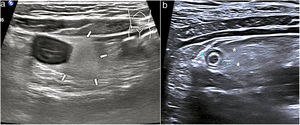

Un patrón característico es el edema de la muscularis-mucosae, en el que la capa más superficial adquiere una apariencia quística de las válvulas conniventes o edema de los pliegues de Kerckring (fig. 3). Este hallazgo se ha descrito en una serie de patologías, generalmente agudas, reversibles y benignas (tabla 1)29–31. Dada la variedad de etiologías, su interpretación debe realizarse en el contexto clínico y evolutivo.

Imagen longitudinal de un asa de intestino delgado, que muestra un engrosamiento hipoecoico de apariencia quística de las válvulas conniventes (flechas finas), que representa edema en las capas superficiales, con la submucosa fina (flecha gruesa). Las pruebas serológicas confirmaron que se trataba de una ileítis por anisakis.